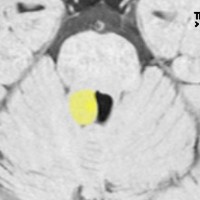

第4室床過誤腫の典型例です

新生児期より動作停止と右眼瞼のちく搦,4ヶ月で右眼の閉眼と口角の引きつれ(顔面けいれん)が目立つようになりました。2歳時には数十秒ごとに発作を繰り返していました。

MRIでは橋の背側(第4脳室床)にT1/T2で等信号の隆起(腫瘤)がみられました。